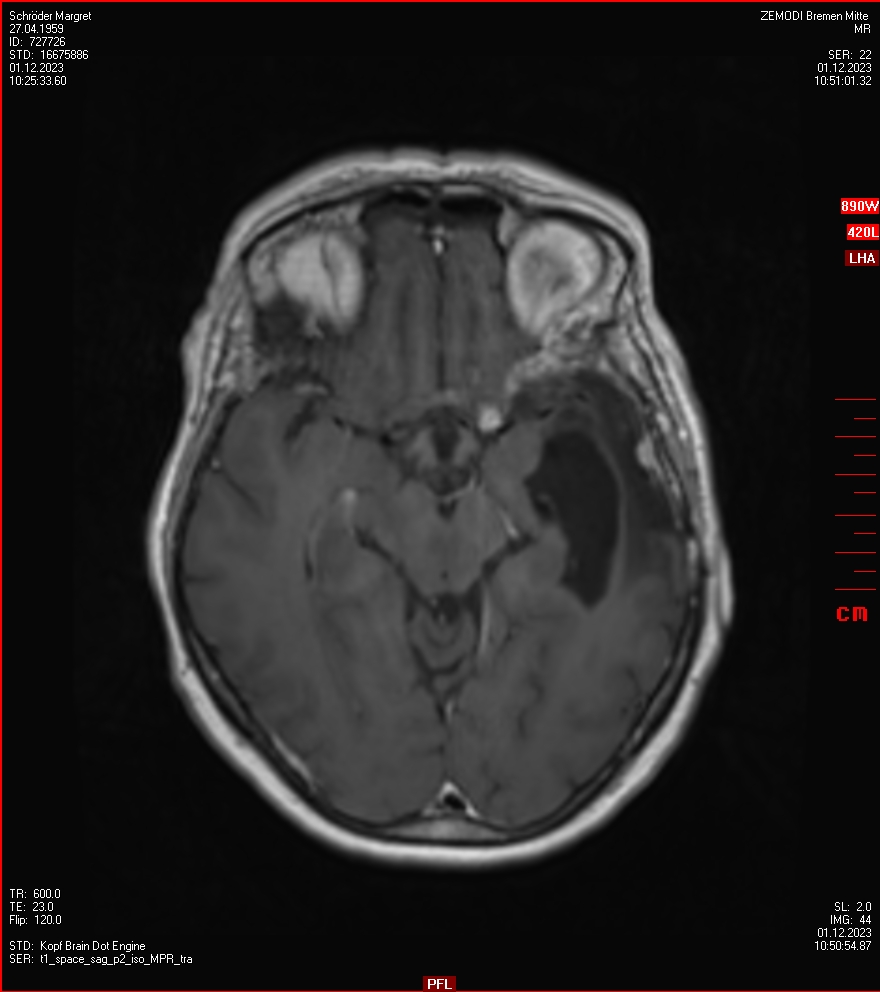

Die letzten drei Bilder Zeigen aus meiner Sicht den Tumor, der im Jahr 2021 bestrahlt wurde.

Zum Vergleich nun auch die Bilder vom 1.12.2023:

Ich denke, in den letzen 12 Monaten sind da ein paar Rezidive gewachsen,  vor 12 Monaten waren sie auch schon zu erkennen - vorher noch nicht. Nun hoffe ich auf den Rat des Spezialisten. Hoffendlich kann man etwas machen.